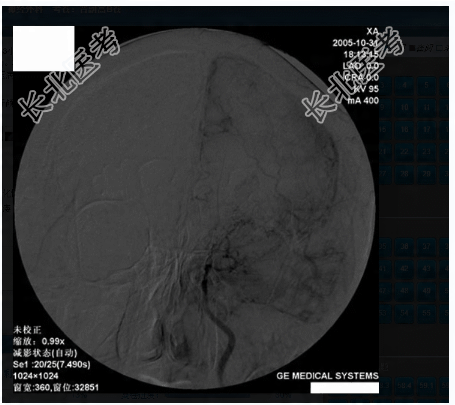

- 多项选择题3.提示:患者急诊行开颅探查、血肿清除、去骨瓣减压术, 术后一周后行全脑血管DSA,见下图。从上可能得出的诊断有

A、前交通动脉瘤

B、脑动静脉畸形

C、脑动脉粥样硬化性狭窄

D、硬脑膜动静脉瘘

E、烟雾病

F、海绵状血管畸形